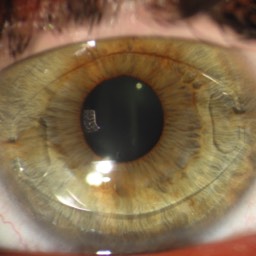

Quelques pathologies ophtalmologiques du segment antérieur